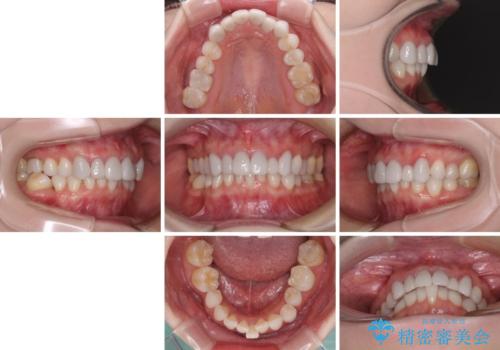

前歯のデコボコと奥歯の咬み合わせをインビザラインで改善

- 上下前歯のデコボコと奥歯の欠損を気にして来院された患者様です。

右下の欠損分は奥歯が倒れ込んでスペースがなくなっていたため、矯正治療により本来の位置に歯を移動させ、オールセラミックブリッジによる欠損補綴治療を行うこととしました。

全顎的にセラミッククラウンが多く装着されているため、インビザラインによる矯正治療を行うこととしました。

右下は移動量が多いため、十分な移動が達成されない場合はワイヤー装置を使用する予定としておりましたが、しっかりとマウスピースを装着してくださったため、前歯とともに十分に歯を動かすことができました。